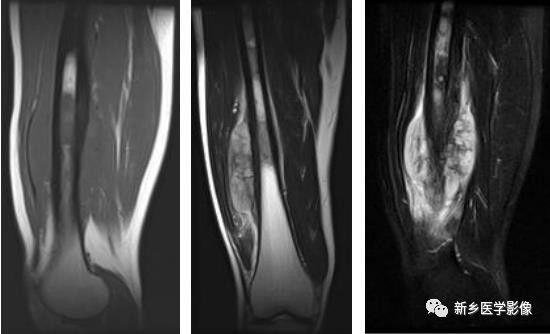

骨质破坏MRI图像

股骨中下段MRI T1WI矢状面(a)、T2WI冠状面(b)和T2WI矢状面脂肪抑制(c)图像示股骨下段髓腔内多发不规则异常信号(相对于骨髓),软组织肿块,为骨肉瘤。